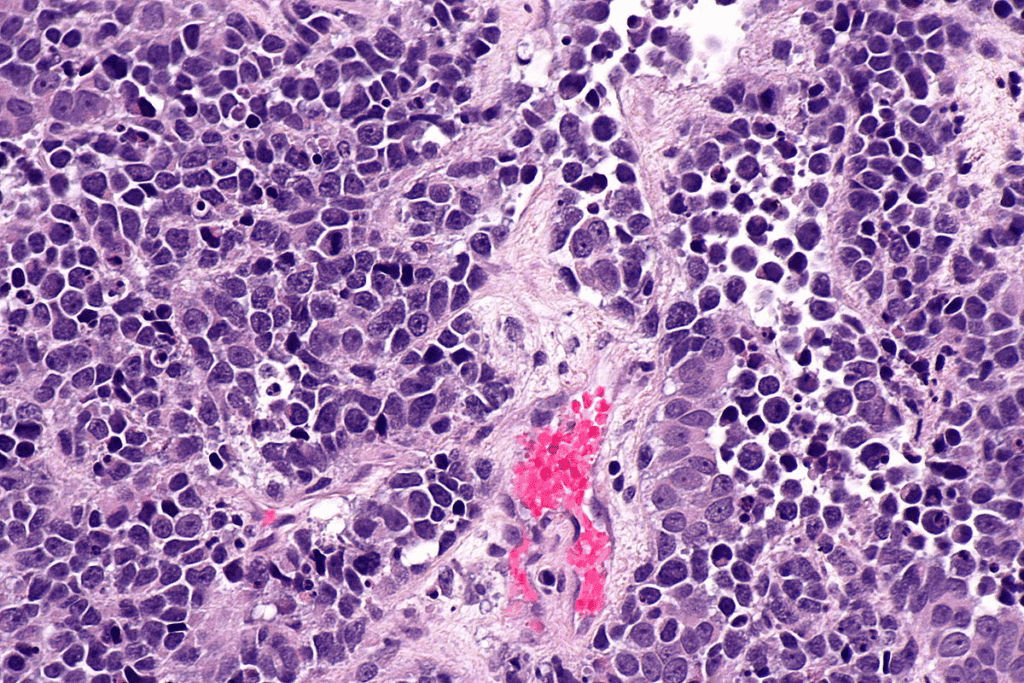

Types and Development of Bladder Cancer

Bladder cancer is divided into types based on where it starts. The most common is transitional cell carcinoma, or urothelial carcinoma. It begins in the bladder’s lining cells. Less common types include squamous cell carcinoma and adenocarcinoma, each with its own risk factors.

Bladder cancer develops from genetic changes in bladder cells. These changes cause cells to grow out of control. Many factors can influence this, like genetics, environment, and lifestyle.